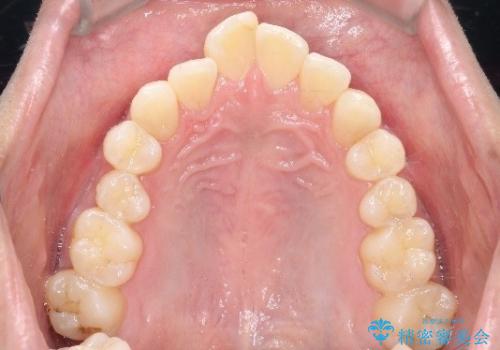

初診時の歯並びの状態としては、上下ともに前歯部の中等度のがたつきがあり、上の前歯が重なっている状態でした。

また元々下の前歯は1本少なく、歯の本数が少ないことを前提とした矯正治療を行いました。

抜歯は必要なく、マウスピース矯正にて治療を行っています。